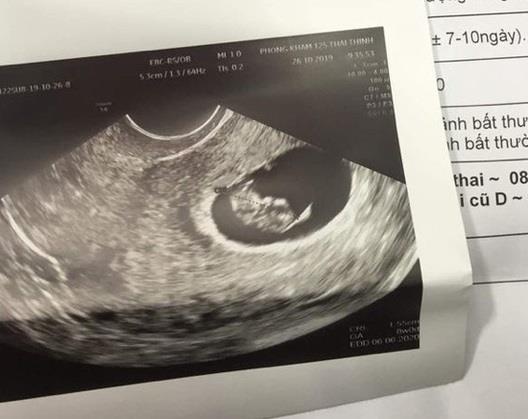

Ngày 26/9, bệnh nhân Đ.T.N.A. (28 tuổi, ngụ Hà Nội) đến Thẩm mỹ viện Sophie International (253A Hoàng Sa, phường Tân Định, quận 1, TP.HCM) tư vấn dịch vụ hút mỡ bụng. Sau đó, bệnh nhân được đưa đến Bệnh viện Thẩm mỹ EMCAS để làm xét nghiệm và tiến hành phẫu thuật hút mỡ, căng da bụng.

Sau phẫu thuật, bệnh nhân trở về Hà Nội thì có biểu hiện chóng mặt, buồn nôn, khó thở. Sau khi khám tại bệnh viện tư, bệnh nhân phát hiện đã mang thai 8 tuần.

Gia đình bệnh nhân cho biết cả thẩm mỹ viện lẫn bệnh viện đều không có động thái chia sẻ, quan tâm đến chị N.A., trong khi sức khỏe bệnh nhân đang rất yếu, nguy cơ phải bỏ thai nhi.